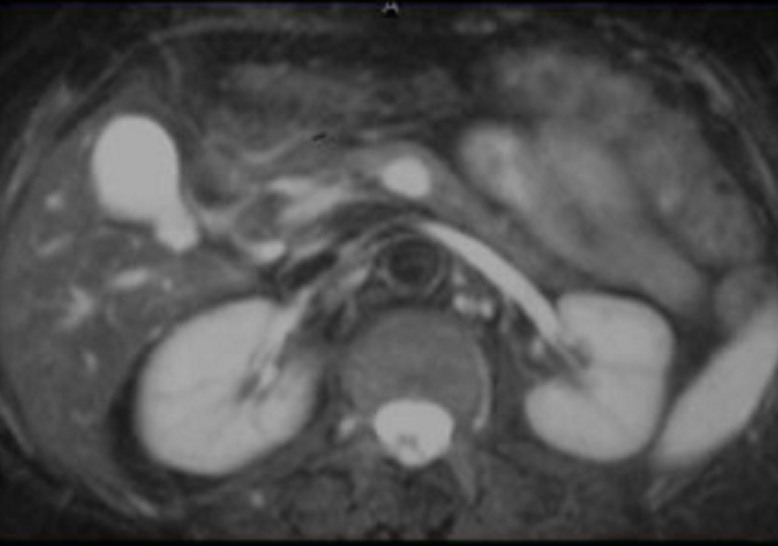

L'IRM : C'est technique

hypervascularise et hypersignal .

Meme cas en coupe IRM

ponderation T1 apres injection de Gadolinium

IRM plus C+(Gd) . La tumeur hypervacularisee devient

hyperdense a la phase aterielle , les tumeurs de

forme fibreuse avait le temps de rehaussement

plus tardive |